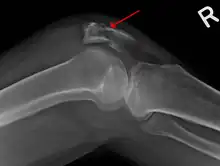

| A fracture of the patella seen on a lateral view | |

Vertical patella fracture